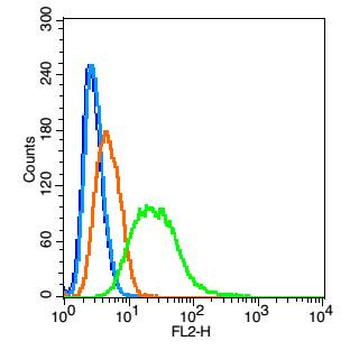

Anti-Cyclophilin A/PPIA Antibody [orb19174]

FC, ICC, IF, IHC, IHC-Fr, WB

Human, Mouse, Rat

Rabbit

Polyclonal

Unconjugated

10 μg, 100 μgCYPA Rabbit Polyclonal Antibody [orb100498]